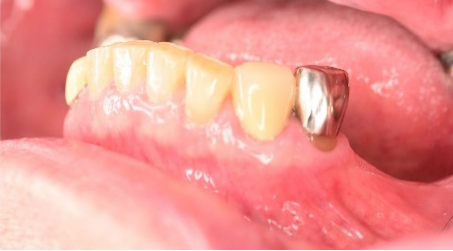

Before

抜いた歯 真二つにわれています

After

治療内容

右下のブリッジの支台になっている前方の歯が、歯根破折を起こしていましたので抜歯しました。インプラントを右下第一、第二大臼歯部に2本埋入しました。

所感

実はこの患者さんは、2014年に右下の第二大臼歯(一番奥の歯から2番目の歯)を歯根破折により抜歯し、その際の治療法としてブリッジを選択されました。そして今回、ブリッジを支えていた歯(第一大臼歯)がついに歯根破折を起こしてしまいました。

ブリッジは、3本分の歯を2本の歯で支えるため、支える歯の負担が大きくなり、歯根破折を起こす危険性が高くなります。

今回の抜歯後は、歯が2本ない状態になるので、そこを補う方法についてご説明しました。選択肢は再度ブリッジを入れるか、インプラントになります。ブリッジにして支える歯がまた折れてしまうと歯が3本ない状態になる可能性があるため、インプラントを選択されました。もし11年前にブリッジではなくインプラントを選んでおられたら、今回の歯根破折や抜歯は起きなかったかもしれません。ブリッジは、噛む力の強い方、歯ぎしりをする方、硬い食べ物が好きな方は、支えの歯の負担がより大きくなるのでおすすめできません。

インプラントは、それ自身が単独で植立しているので、他の歯に負担がかかりません。インプラントは、欠損を補う最良の方法と考えます。

インプラント2本:¥726,000(税込)